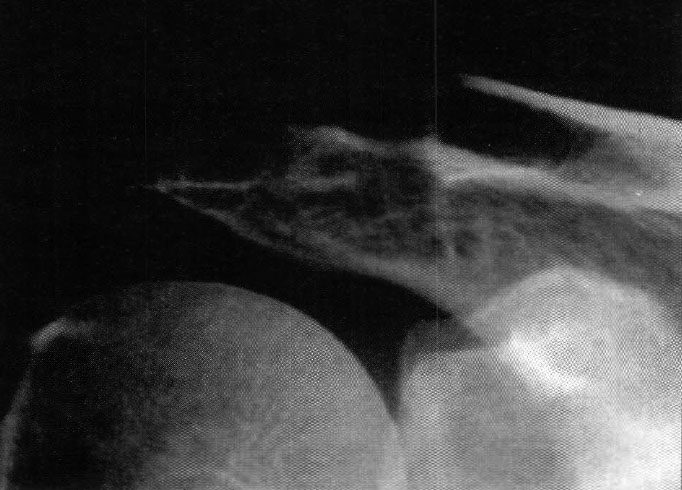

Foto 8: Radiografía preoperatoria. Artrosis con pinzamien-

Foto 9: Radiografía postoperatoria. Margen de resección satisfactorio (11 mm).

En los primeros casos recomendamos el control radiológico intraoperatorio con intensificador de imágenes para asegurar una resección satisfactoria (Fotos 8 y 9).

La cantidad de hueso clavicular resecado osciló entre 10 y 25 mm. En un caso la resección fue excesiva (aprox. 30 mm.) y en otro caso quedó un fragmento de hueso sin resecar en la zona postero-superior de la articulación. Ambos casos tuvieron una evaluación excelente y el resultado radiográfico no influyó en en el control clínico.